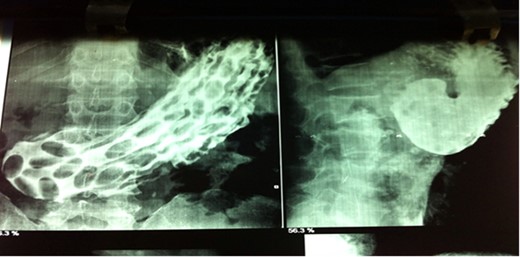

Keeping Crohn’s as diagnosis patient was given mesalamine 400 mg tid by gastrophyscian. But patient didn’t respond so the Patient was advised surgical management. Barium meal follow through (BMFT) (Fig. 1), reported multiple hyperplastic polyps with gastric outlet obstruction (GOO). Repeat UGI endoscopy revealed multiple pills (mesalamine) in the stomach with GOO (Fig. 2). Around 40 pills were extracted with the help of flower basket, and then patient underwent laparoscopic management of GOO. Surgical procedure done was laparoscopic gastrojejunostomy (Fig. 3). Patient also underwent left and right truncal vagotomy (Fig. 4).